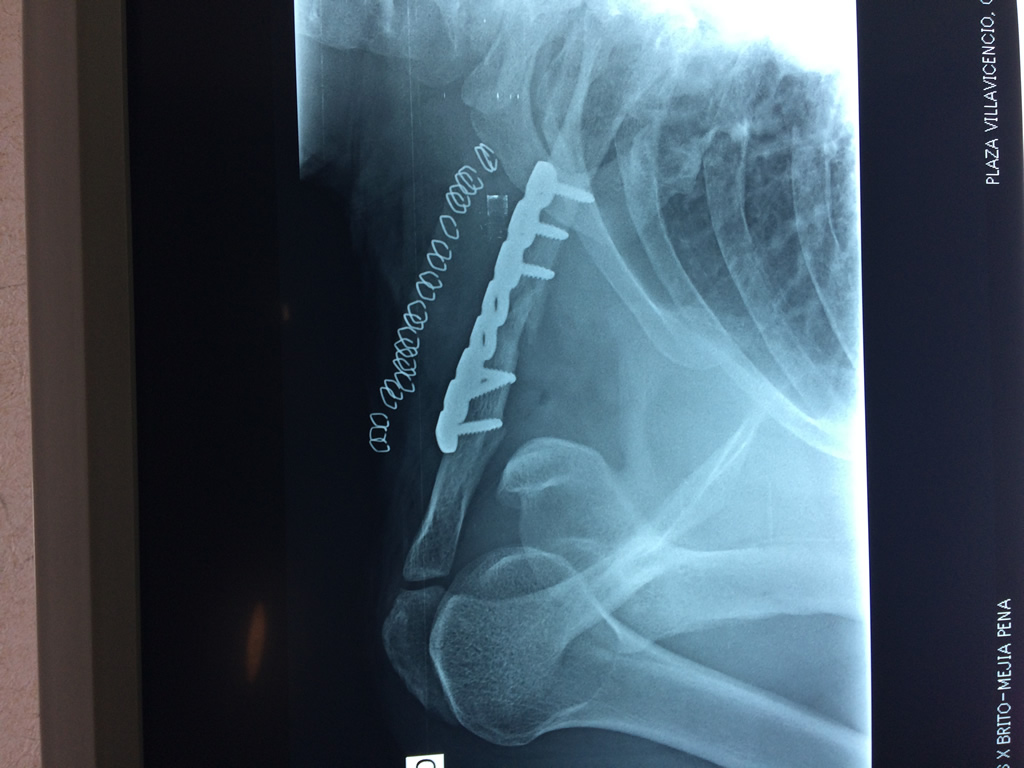

Cirugía de Fémur - Clavícula

La clavícula es un hueso largo, con forma de "S" itálica, situado en la parte anterosuperior del tórax. Junto con la escápula forman la cintura escapular. Se puede palpar por toda su longitud y se extiende del esternón al acromion de la escápula, siguiendo una dirección oblicua lateral y posterior.

Se considera el único medio de unión entre el miembro superior y el tórax. A pesar de su aspecto, similar al de un hueso largo, posee una estructura semejante a la de un hueso plano, ya que carece de epífisis y de diáfisis, lo que la harían entrar dentro de la clasificación de hueso largo. Carece de un canal medular propiamente dicho.